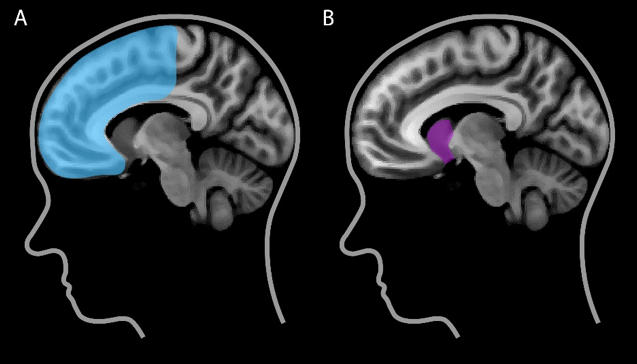

Twee gebieden in onze hersenen lijken cruciaal voor feedback leren: het striatum en de frontale cortex (Maia, 2009). Het striatum ligt diep in de hersenen (Figuur 1a) en signaleert in hoeverre de daadwerkelijke gevolgen van een keuze prettiger of minder prettig uitvallen dan je van tevoren verwachtte. De frontale cortex bevindt zich aan de voorkant van de hersenen achter het voorhoofd (Figuur 1b) en is betrokken bij doelgericht gedrag: het maken van (een reeks) keuzes met een bepaald doel voor ogen. Succesvolle keuzes kunnen echter alleen worden gemaakt als de betrokken hersengebieden goed met elkaar communiceren. Dat hangt onder andere af van hoe goed deze gebieden fysiek met elkaar verbonden zijn (Kanai en Rees, 2011). Vergelijk het met de snelweg tussen Amsterdam en Utrecht: hoe breder de weg, hoe meer auto’s er per uur overheen kunnen.